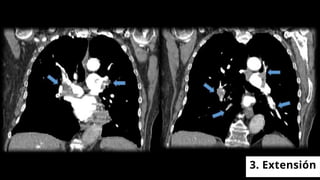

1. REPLECIÓN

Localización en el vaso

Morfología

Ángulo con respecto a la luz

3. Extensión